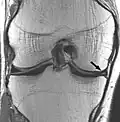

Proton density weighted PD Long TR (to reduce T1) and short TE (to minimize T2).[70] Joint disease and injury.[71]